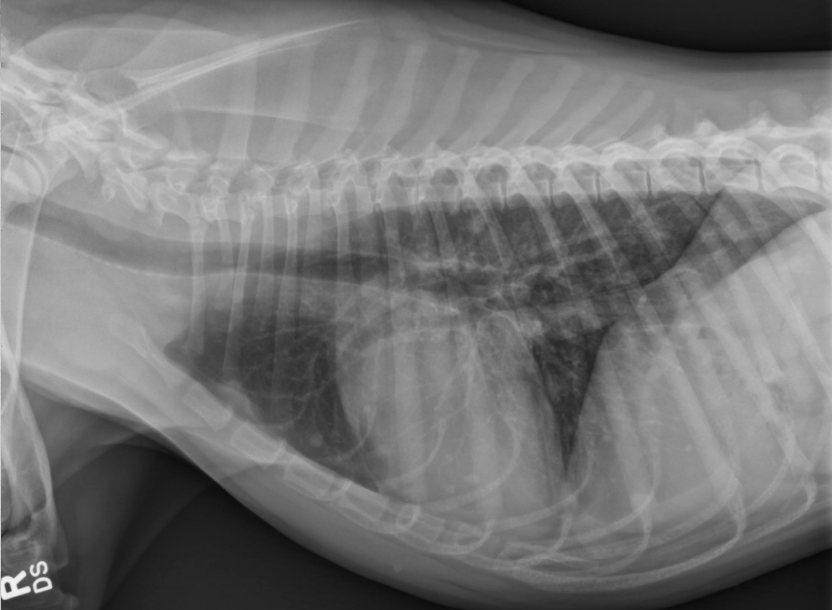

● 12 yo dog

● Coughing for 2 months

alveolar pattern caudodorsally (black tree visible)

fat in ventral thorax

cardiac silhouette lifted and rounded, maybe free fluid

on VD: mass effect